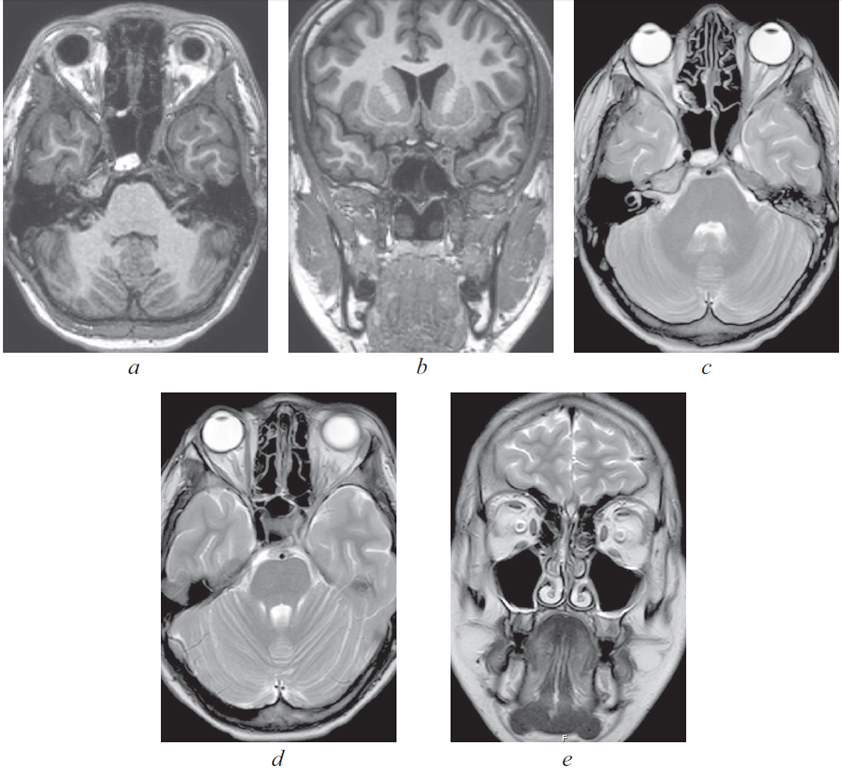

Риногенные внутричерепные осложнения, такие как абсцесс головного мозга и тромбоз вен и синусов головного мозга, по сей день остаются грозной, жизнеугрожающей патологией, не редко заканчивающейся летальным исходом, несмотря на широкое развитие антибактериальной терапии и приверженность пациентов к проводимому лечению. Нередко причиной развития внутричерепных осложнений служит обострение хронического воспалительного процесса в придаточных пазухах носа, тогда как острая ЛОР-патология синусов приводит к развитию риногенных осложнений лишь в небольшом проценте случаев. К сожалению, высокое развитие лучевой и лабораторной диагностики не всегда позволяет вовремя диагностировать данные состояния и оказать адекватную хирургическую помощь. В детском и подростковом возрасте важно выполнить своевременное полное и в то же время малоинвазивное, не приводящее к инвалидизации, хирургическое пособие. Анализ зарубежной литературы последних лет показывает, что нейрохирургические операции в различном объеме (от трепанопункции головного мозга до краниотомии) встречаются в подавляющем большинстве случаев лечения риногенных внутричерепных осложнений. В статье приводятся два клинических случая успешно пролеченных в отделении оториноларингологии Санкт-Петербургского государственного педиатрического медицинского университета пациентов с внутричерепными осложнениями без высокотравматичной нейрохирургической операции. Комбинация эндоназальной эндоскопической операции и массивной адекватной консервативной терапии (антибиотикотерапия в сочетании с применением антикоагулянтов при синус-тромбозе) позволяет добиться выздоровления пациента без обращения к нейрохирургическому вмешательству.